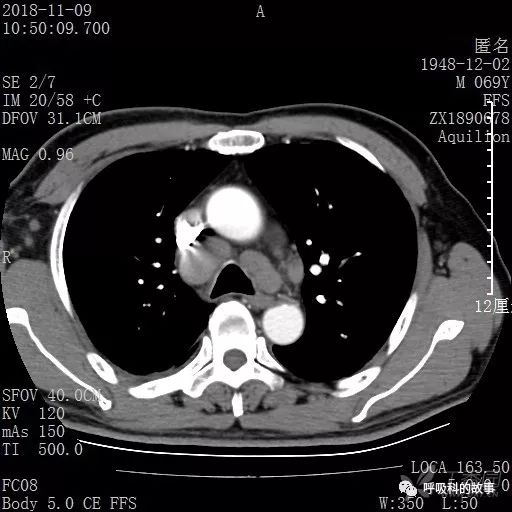

胸部增强CT示右肺门占位伴远端阻塞性肺炎,纵膈、右肺门、右侧颈根部、右侧腋下及肝门部肿大淋巴结。两侧胸腔少量积液。

纵隔窗的增强CT